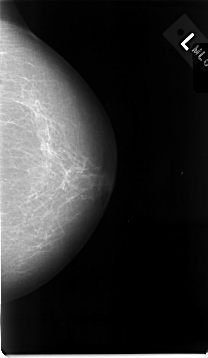

ics_version 1.0 filename C-0014-1 DATE_OF_STUDY 22 6 1992 PATIENT_AGE 83 FILM FILM_TYPE REGULAR DENSITY 1 DATE_DIGITIZED 11 9 1997 DIGITIZER LUMISYS LASER SEQUENCE LEFT_CC LINES 4648 PIXELS_PER_LINE 2696 BITS_PER_PIXEL 12 RESOLUTION 50 NON_OVERLAY LEFT_MLO LINES 4632 PIXELS_PER_LINE 2824 BITS_PER_PIXEL 12 RESOLUTION 50 NON_OVERLAY RIGHT_CC LINES 4608 PIXELS_PER_LINE 2624 BITS_PER_PIXEL 12 RESOLUTION 50 OVERLAY RIGHT_MLO LINES 4664 PIXELS_PER_LINE 2800 BITS_PER_PIXEL 12 RESOLUTION 50 OVERLAY |